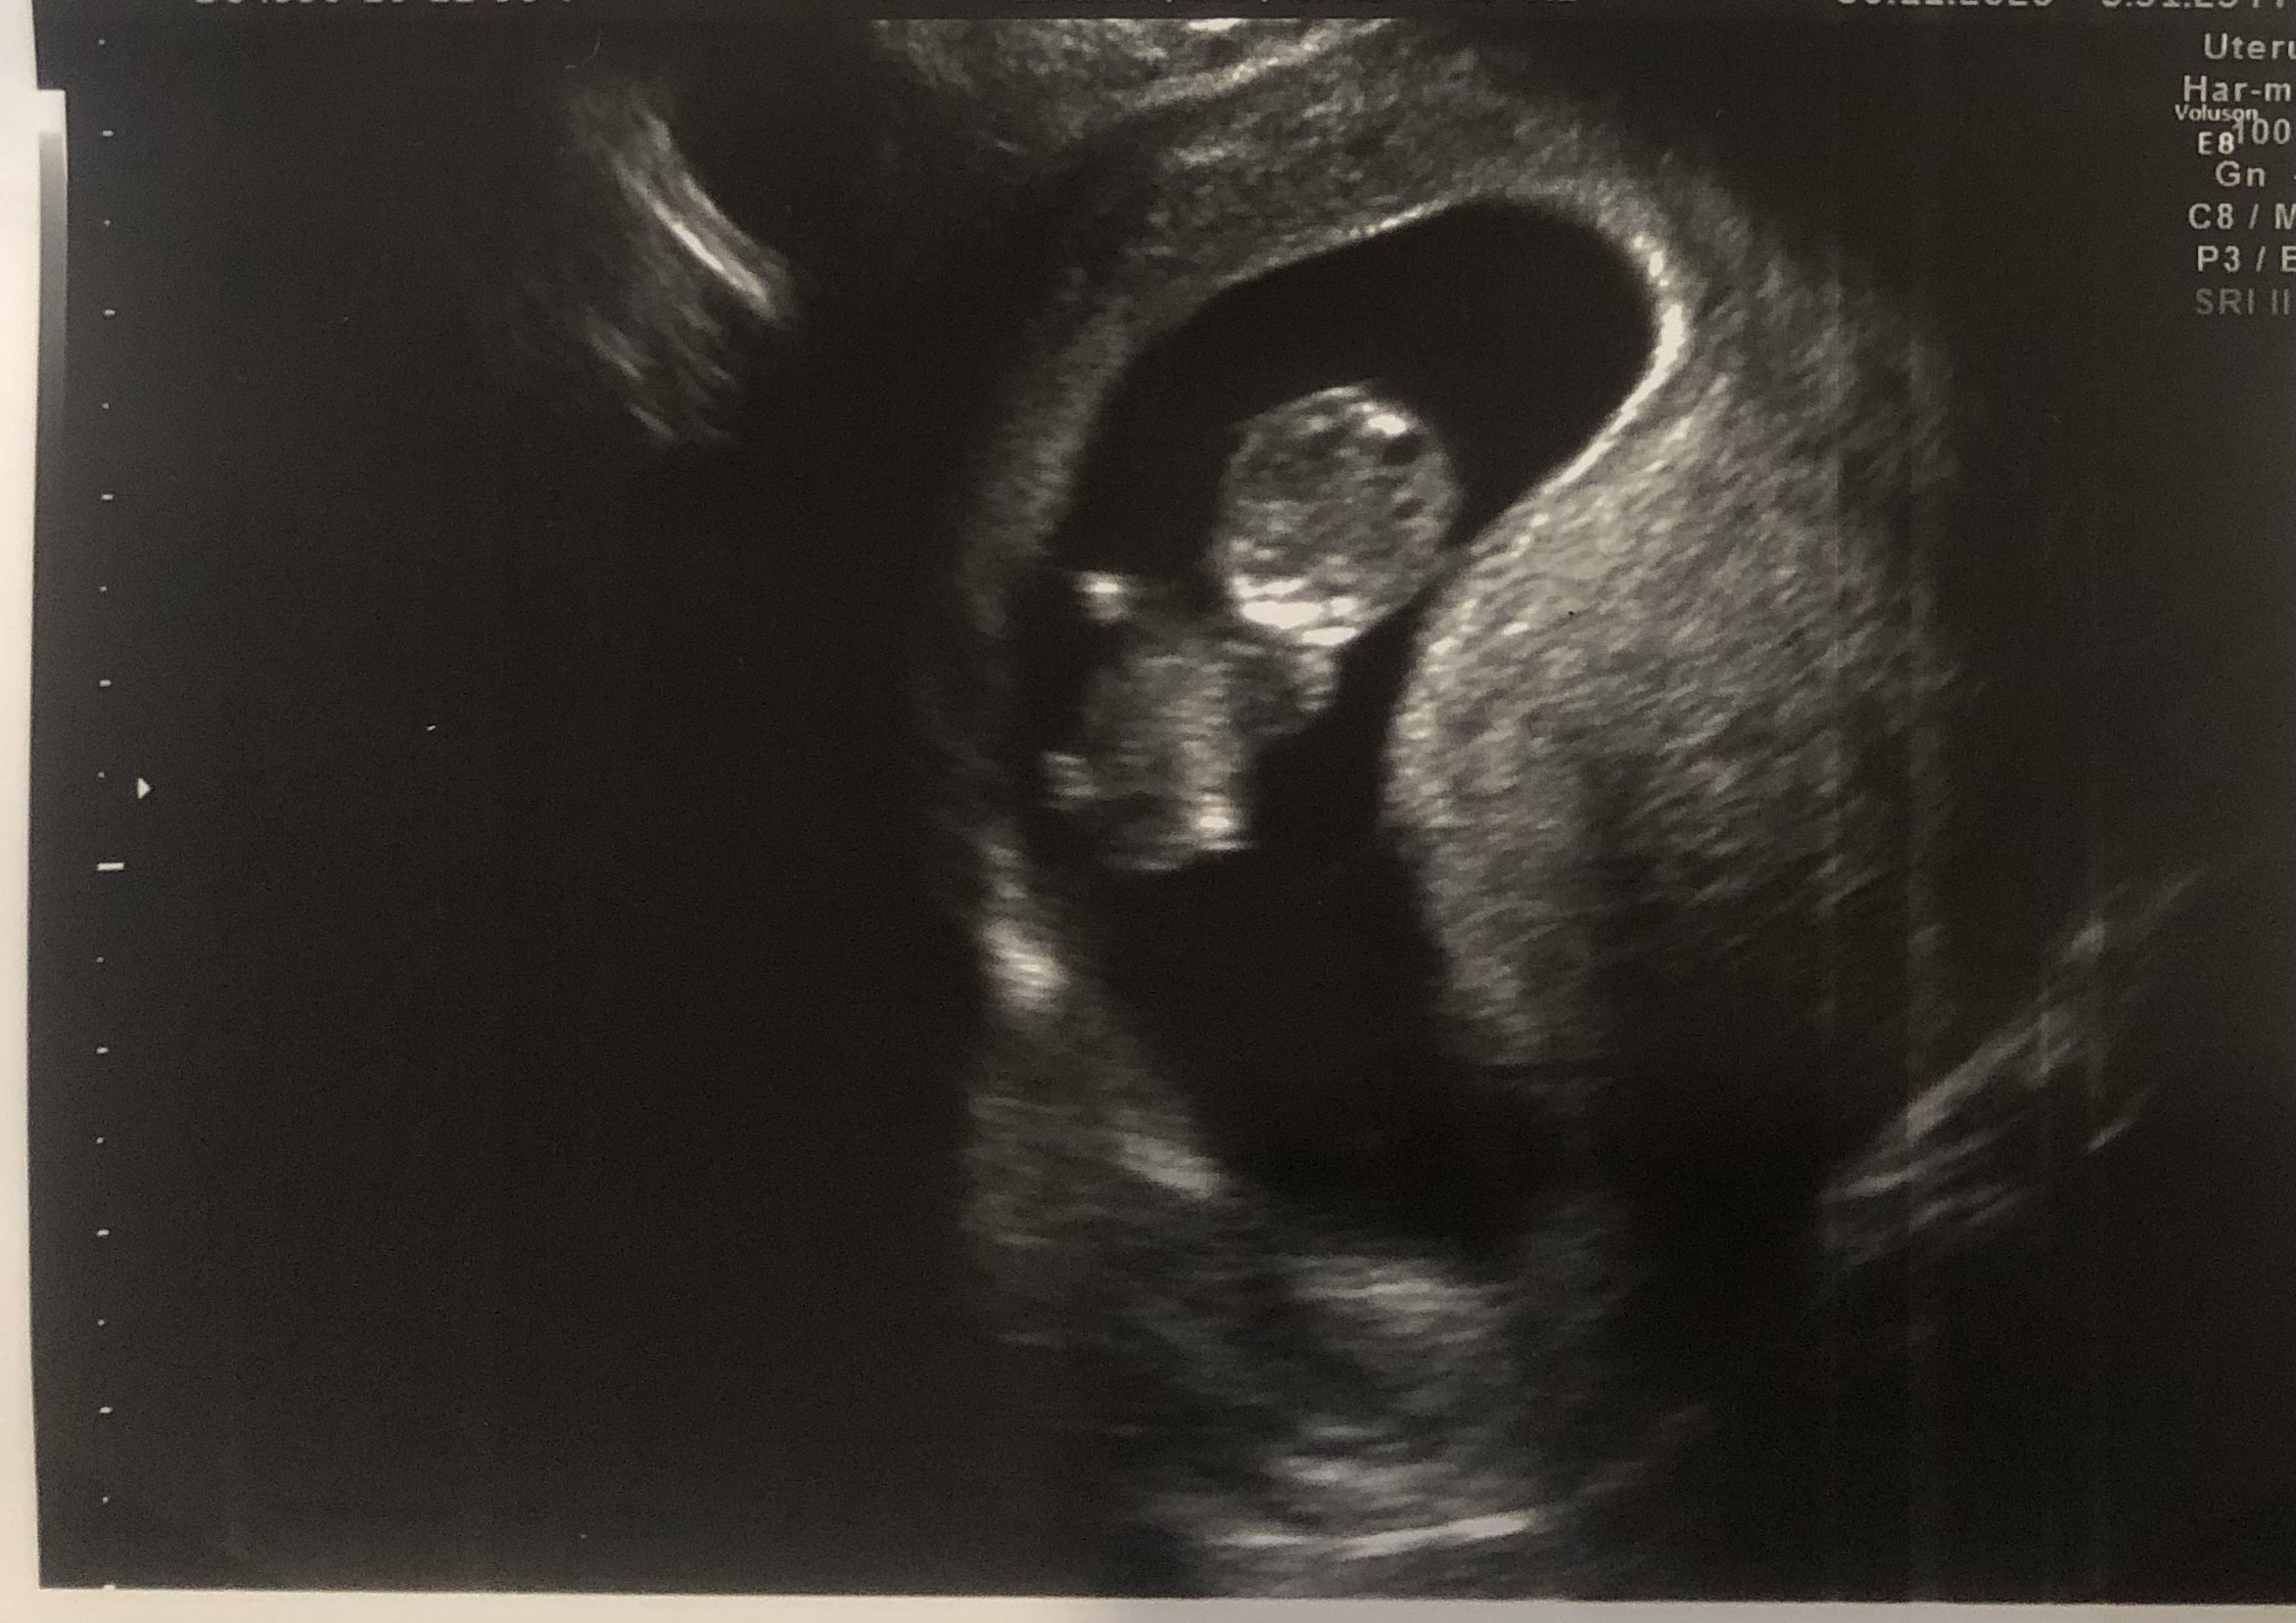

5+3, pęcherzyk z ciałkiem żółtym. :)

• IMG_7638.jpg

123,2 KB · Wyświetleń: 365